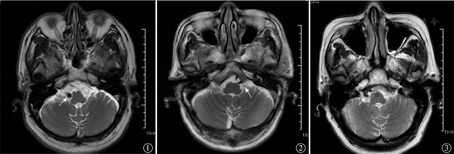

病例1:患者男性,63岁。因发作性眩晕3年、加重3个月入院。患者3年前于站立时出现眩晕,无耳鸣、听力减退,与转动头颈无关,未诊治。近3个月,患者眩晕较前明显加重,站立、行走或转身时即出现,伴双下肢无力,每日发作数十次,持续数十秒至2~3 min缓解。既往有重症肌无力病史。入院查体:生命体征平稳,神清语利,眼球运动正常,有复视,无眼震;双耳听力粗测正常,变位眼震试验(Dix-hallpike test)(-),甩头试验(head-thrust test)(-);心、肺、腹查体大致正常;头颅MRI平扫:右椎动脉扩张迂曲,于右侧延髓处形成压迹(图1);脑干听觉诱发电位(BAEP):左耳Ⅰ波潜伏期延长,双耳Ⅰ~Ⅲ波波峰间期延长;前庭功能检查:视动中枢结果异常,双侧水平半规管功能正常。住院期间予患者改善微循环、改善复视症状后眩晕仍未好转,后予卡马西平200 mg、2次/d口服,患者眩晕发作减少。因患者HLA-B*1502基因3个位点均为突变杂合型,使用卡马西平出现相关不良反应风险增高,遂改为丙戊酸钠200 mg、3次/d口服,患者症状明显好转出院,随访9个月症状未发。

病例2:患者男性,69岁。因反复眩晕1年就诊于我院门诊。患者1年前无明显诱因出现反复眩晕发作,伴有视物旋转、恶心、左耳听力下降,眩晕每次发作时间持续10~15 s,伴恶心,无呕吐。当地医院以良性阵发性位置性眩晕予多次手法复位,症状无改善。门诊完善前庭功能检查:视动中枢正常,位置试验未见异常,双水平半规管功能正常。头颅MRI:双侧椎动脉、基底动脉走行迂曲,左侧小脑前下动脉压迫推移左侧前庭神经(图2)。患者HLA-B*1502基因3个位点均为野生型,予卡马西平200 mg、2次/d口服,患者眩晕症状明显好转,随访7个月症状未发。

病例3:患者女性,75岁。因反复眩晕2年入院。患者2年前无明显诱因出现反复眩晕发作,伴有视物旋转、恶心,右耳持续性高音调耳鸣、右耳听力下降及轻度耳闷堵感,耳鸣于眩晕发作前有加重,每次发作持续约10 s。既往有高血压病史,口服降压药物血压控制良好。入院查体:生命体征平稳,神清语利,粗测右耳听力较左耳下降;心、肺、腹查体大致正常。入院后完善前庭功能检查:视动中枢正常,位置试验未见异常,双水平半规管功能正常;头颅MRI:双侧椎动脉走行迂曲,右侧椎动脉扩张,于外髓处形成压迹,与前庭神经关系密切(图3)。予卡马西平200 mg、2次/d口服,患者眩晕症状明显好转出院,随访3个月症状未见发作。

目前VP的病因尚不明确,多数学者认为其发病机制与三叉神经痛和面肌痉挛相似,即神经血管交互压迫(NVCC),为血管局部压迫前庭蜗神经(vestibular nerves,VN)[1],并以单侧NVCC最常见[6]。经统计,引起VP最常见的责任血管为小脑前下动脉[5],小脑后下动脉、椎动脉、基底动脉少见[7],也有椎基底动脉迂曲、扩张致病的报道[8,9]。这些血管与VN存在3种关系:无接触关系、接触关系、推移关系,NVCC为后两者。VN出脑干受压后易发生异常放电,导致动作电位在相邻的神经间过度传递而引起眩晕。病例1和病例3均呈现椎基底动脉迂曲扩张表现,与一侧VN呈接触关系或推移压迫关系,病例2见小脑前下动脉与一侧VN呈推移关系,推测这是导致VP的主要病理原因。